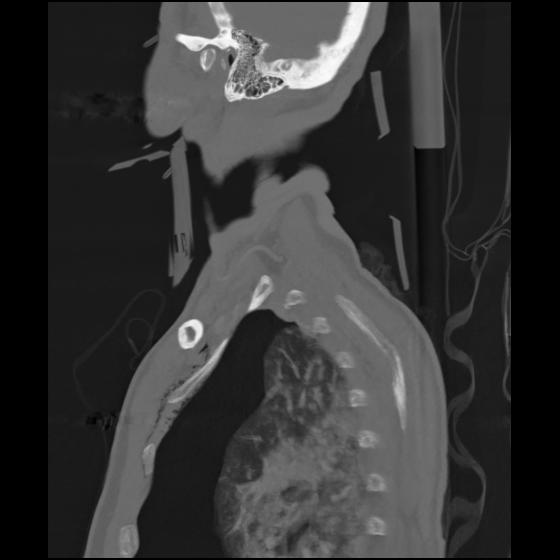

24 ANGIO,CE,Sag-MIP,5.000,ANGIO,Sag-MIP,